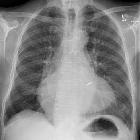

nicht verwechseln mit: Antler sign (lung)The stag's antler sign, also known as the hands-up or inverted moustache sign, refers to upper lobe pulmonary venous diversion in pulmonary venous hypertension or pulmonary edema as seen on an erect frontal chest radiograph.

The prominence of upper lobe pulmonary veins resembles a stag's antlers. It is the earliest sign of pulmonary venous hypertension (grade 1 pulmonary edema).

The commonest causes of stag antler sign on chest x-ray are :

- left heart failure

- fluid overload